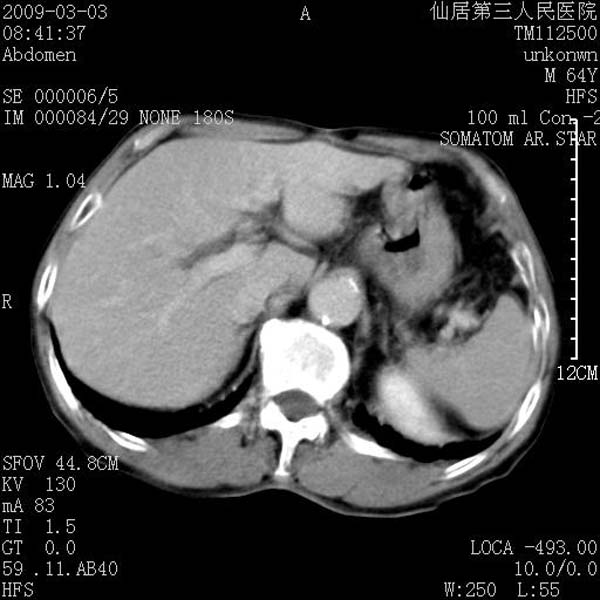

标题: CT18469:男性,64y,体检B超示肝脏低回声肿块,有胃溃疡手术 [打印本页]

患者,男性,64y,体检b超示肝脏低回声肿块,有胃溃疡手术史。

从平扫及增强的特点来看,支持肝脏腺瘤并出血。

ct值呢?感觉没强化,象囊性。

支持肝脏腺瘤并出血。期待结果

考虑高密度囊肿可能性大

考虑高密度囊肿可能性大支持